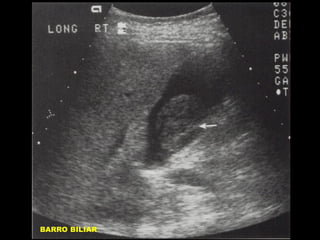

MATERIAL SIMILAR A TEJIDO

BLANDO INTRAVESICULAR

• AYUNO CRONICO/COLECISTITIS

•

ACALCULOSA.

OBSTRUCCION VESICULAR

HEMORRAGIA VESICULAR / DETRITUS

POR INFECCION.

POLIPOS VESICULARES

CARCINOMA / METASTASIS

LITOTRIPSIA EXTRACORPOREA

ARTEFACTOS.

BARRO BILIAR